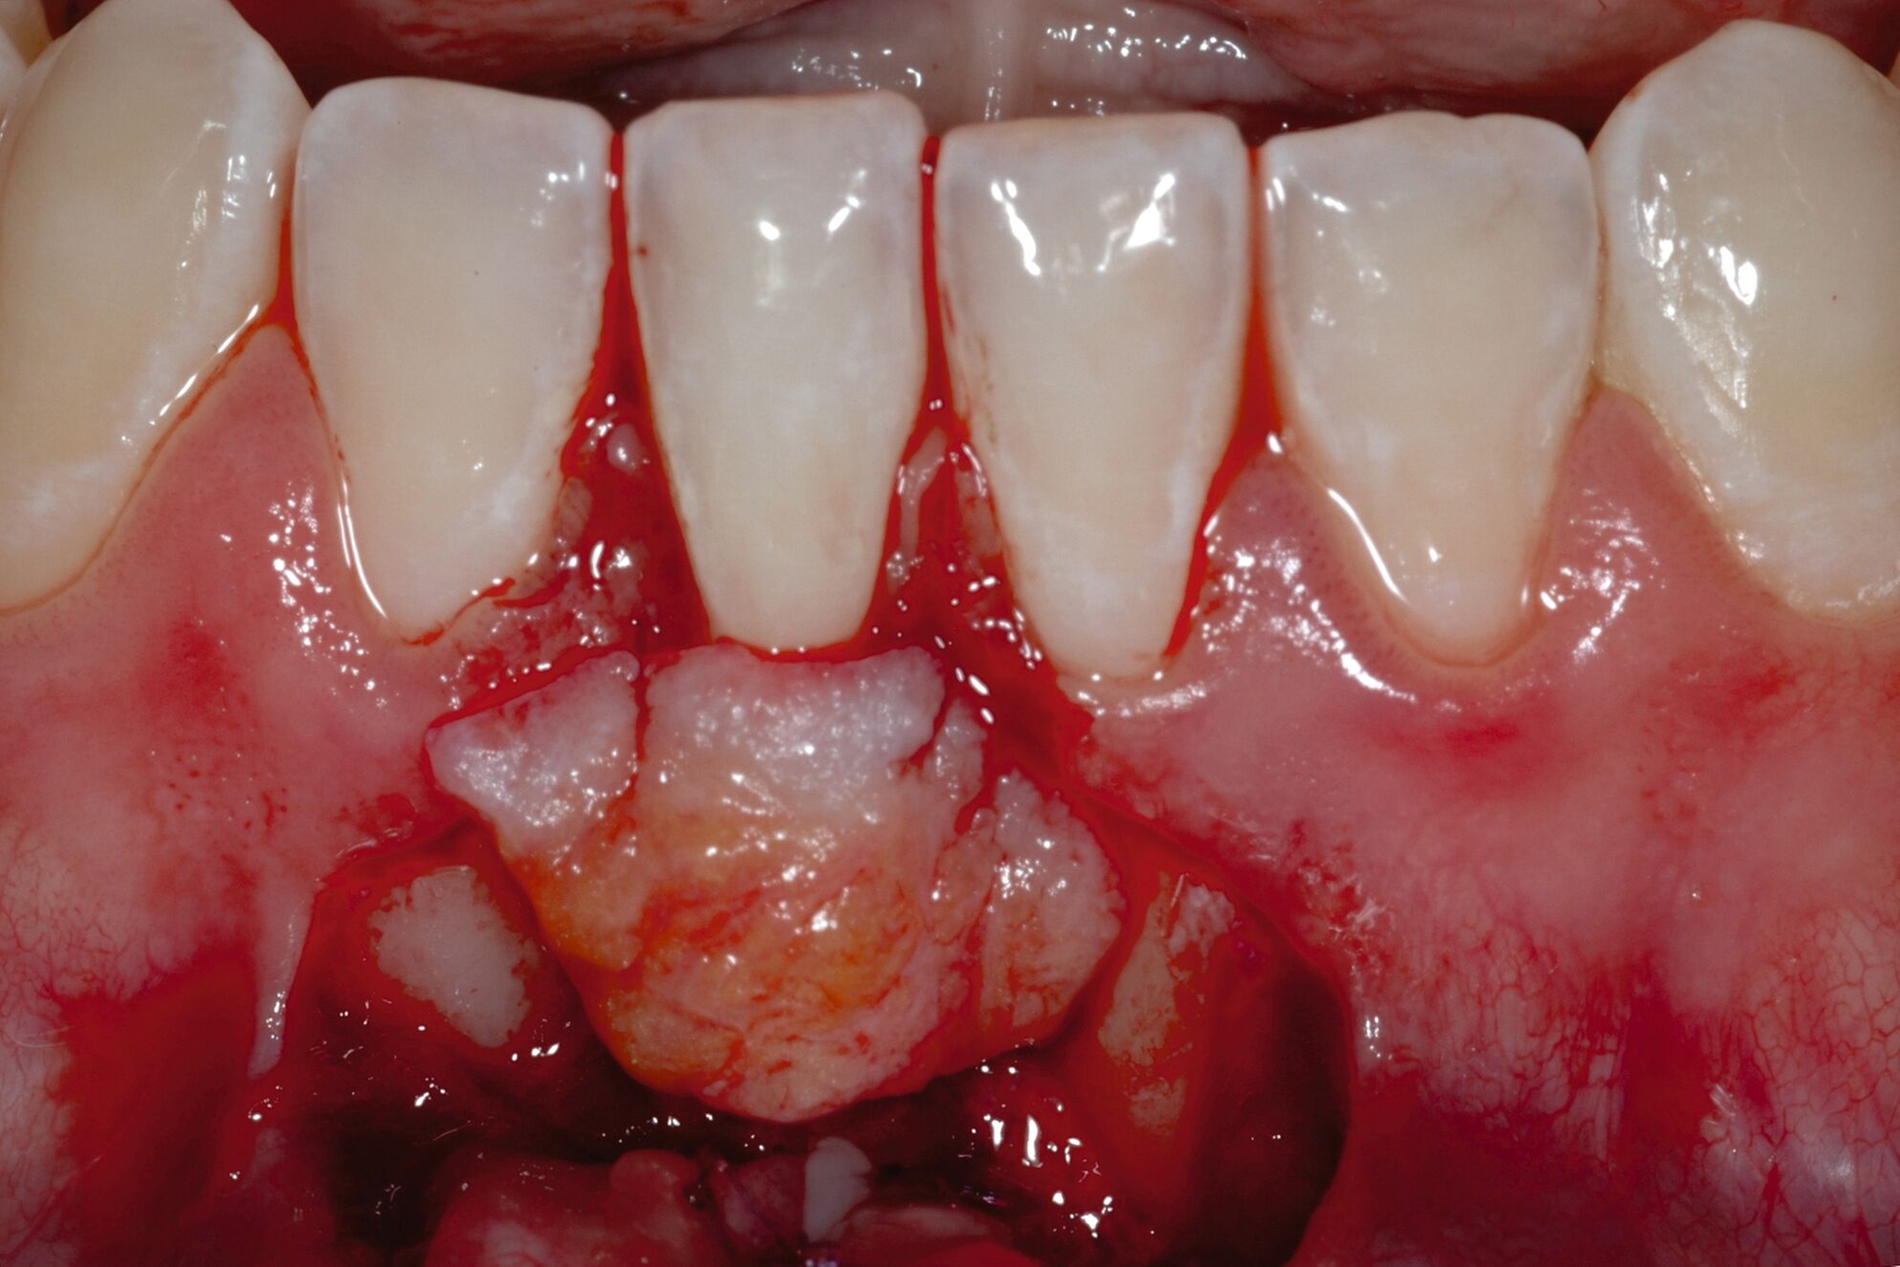

Tunkel et al. versuchten die Vorteile von Zucchellis Koronalem Verschiebelappen und Sculeans Lateral Geschlossenem Tunnel in einer Technik zu vereinen: dem Lateral Geschlossenen Koronalen Verschiebelappen (LCAF) [Tunkel et al., 2024] (Abbildung 3). Bei dieser Methode, mit der vor allem tiefe singuläre parodontale Rezessionen behandelt werden, wird die Koronalverschiebung ohne Entlastungsinzisionen kombiniert mit dem lateralen Verschluss der tiefen parodontalen Rezession.

Das Vorgehen ist hier wie folgt: Zunächst wird im Bereich der tiefen Rezession der Gingivarand geringfügig exzidiert, um ein Zusammenwachsen der geschlossenen Lappenanteile zu ermöglichen. Anschließend wird der Schnitt in horizontaler Richtung durch leicht bogenförmige Schnittführungen auf Höhe der Schmelz-Zement-Grenze erweitert, um mindestens zwei Zähne rechts und links von der Rezession (Abbildung 3b). Im Unterkiefer-Frontzahnbereich, wo die Rezessionen heutzutage am häufigsten vorkommen, sollte der Lappen mindestens von Eckzahn zu Eckzahn gebildet werden, um ein harmonisches Ergebnis nach Abheilung zu erreichen. Auf vertikale Entlastungsinzisionen kann komplett verzichtet werden. Anschließend erfolgt die Lappenpräparation nach dem bereits für koronale Verschiebelappen gängigen Prinzip teilschichtig-vollschichtig-teilschichtig.

Die Papillenbereiche werden mit dem Skalpell scharf vom Periost abgelöst. Dann wird das Periost durchtrennt und bis zur mukogingivalen Grenze ein vollschichtiger Lappen gebildet. Nach Überschreiten dieser wird wieder zweischichtig präpariert. Hierdurch wird eine gute Mobilisation des Lappens erreicht, die eine ausreichende Koronalverschiebung ermöglicht. Entgegen dem in früheren Jahren propagierten komplett teilschichtigen Vorgehen, kann durch dieses Verfahren die Gefahr von Lappenperforationen signifikant gesenkt werden, da diese insbesondere im Bereich der mukogingivalen Grenze auftreten. Nachdem die Lappenareale mesial und distal der Rezession gelöst sind, können diese durch zwei bis drei feine monofile Nähte miteinander verbunden werden (Abbildung 3c). Sobald durch diese Naht ein zusammenhängender koronaler Verschiebelappen entstanden ist, werden die Papillenbereiche koronal des gebildeten Lappens entepithelialisiert. Nach Entnahme eines Bindegewebstransplantats oder entepithelialisierten freien Schleimhauttransplantats wird die Wurzeloberfläche mit EDTA-Gel konditioniert und anschließend werden Schmelz-Matrix-Proteine aufgetragen (Abbildung 3d). Diese bewirken die Bildung eines new attachment und fördern zudem die Wundheilung, was gerade bei den delikaten lateralen Verschiebelappen von Vorteil sein sollte [McGuire und Cochran, 2003; Almqvist et al., 2011; Thoma et al., 2011; McGuire et al., 2016]. Anschließend wird das Transplantat durch Nähte ausgehend vom oralen Papillenbereich fixiert (Abbildung 3e). Zuletzt wird der Lappen mit sogenannten doppelten Umschlingungsnähten im Bereich der Papille durch Zug nach koronal und oral fixiert, was eine perfekte Positionierung ermöglicht [Zuhr et al., 2009] (Abbildung 3f). Hierbei muss darauf geachtet werden, dass der Lappen die Schmelz-Zement-Grenze um mindestens 2 mm überdeckt, um eine hundertprozentige Wurzeldeckung erwartbar zu machen [Pini Prato et al., 2005].

Der Lateral Geschlossene Koronal Verschobene Lappen ermöglicht eine annähernd narbenfreie Deckung singulärer parodontaler Rezessionen durch Verzicht auf vertikale Entlastungsinzisionen (Abbildung 3g). Das Lösen der Papillen im Rahmen der Verschiebung ermöglicht eine deutliche Anhebung des Lappens und somit durch großzügige Überdeckung das Erreichen vollständiger Wurzeldeckungen. Durch den lateralen Verschluss im Rahmen der tiefen, über die mukogingivale Grenze hinausgehenden Rezession kann keratinisierte Gingiva im Bereich dieser hergestellt und eine übermäßige Mobilisation und damit Einschränkung des Vestibulums verhindert werden.